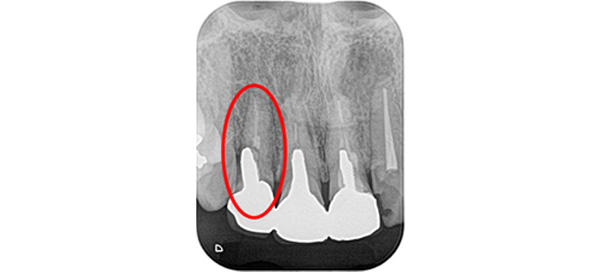

レントゲン写真にもあるようにこの症例では右上の側切歯(前から2番目の歯)の歯根が折れており、抜歯せざるを得ませんでした。

また残りの3本も根管治療(歯の神経の治療)がなされていますが歯根の先に感染がある可能性が高いため再度神経の治療をラバーダム防湿下で行いました。

そして患者さまと相談の上今回はセラミック治療で色味の改善と長期的な安定を図ることとなりました。

精密に歯の形を整え仮歯の形をそれに合わせることによって歯ぐきの状態がきれいに仕上がり、最終的な被せものが入る際に抜歯した箇所が分かりにくく審美的に仕上げていきます。